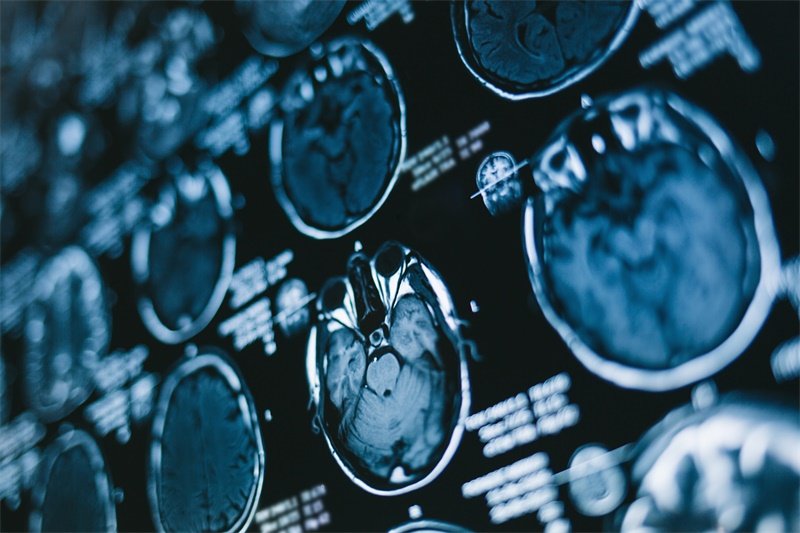

在临床上,囊性占位常因影像学检查而被发现,尤其是MRI或CT扫描。根据其性状,囊性占位可能表现为单一或多个囊泡,大小不一,形态各异。定义的清晰有助于后续的诊断与治疗。

囊性占位的影像学特征是诊断的关键,MRI或CT扫描是最常用的工具。

MRI特征

在MRI影像上,囊性占位通常呈现为信号强度变化的区域。T1加权成像通常显示为低信号或等信号,而在T2加权成像上,囊性区则表现为高信号,周围可能伴有水肿。MRI的高分辨率使得可以清晰观察到囊腔的边界和内部结构。

CT特征

在CT成像中,囊性占位通常表现为低密度区域,边界清晰。如果囊内存在出血或感染,CT图像可能显示复杂的密度变化。在IVP检查中,也可观察到脑脊液动态的变化,所以选择合适的影像学检查非常重要。

影像学检查

影像学检查是确诊的基石,MRI和CT的结合使用可以提供详细的囊性占位信息。针对可疑肿瘤,可能需要进一步的生物活检以明确性质。如果诊断不明确,还可进行脑脊液分析以评估是否存在感染或肿瘤标志物。

影像学检查对于囊性占位的诊断有多重要?

影像学检查是诊断囊性占位的核心工具,能够提供病变的具体位置和性质信息。MRI和CT扫描的结合使用,有助于更好地评估囊性占位的特征,确保准确诊断。